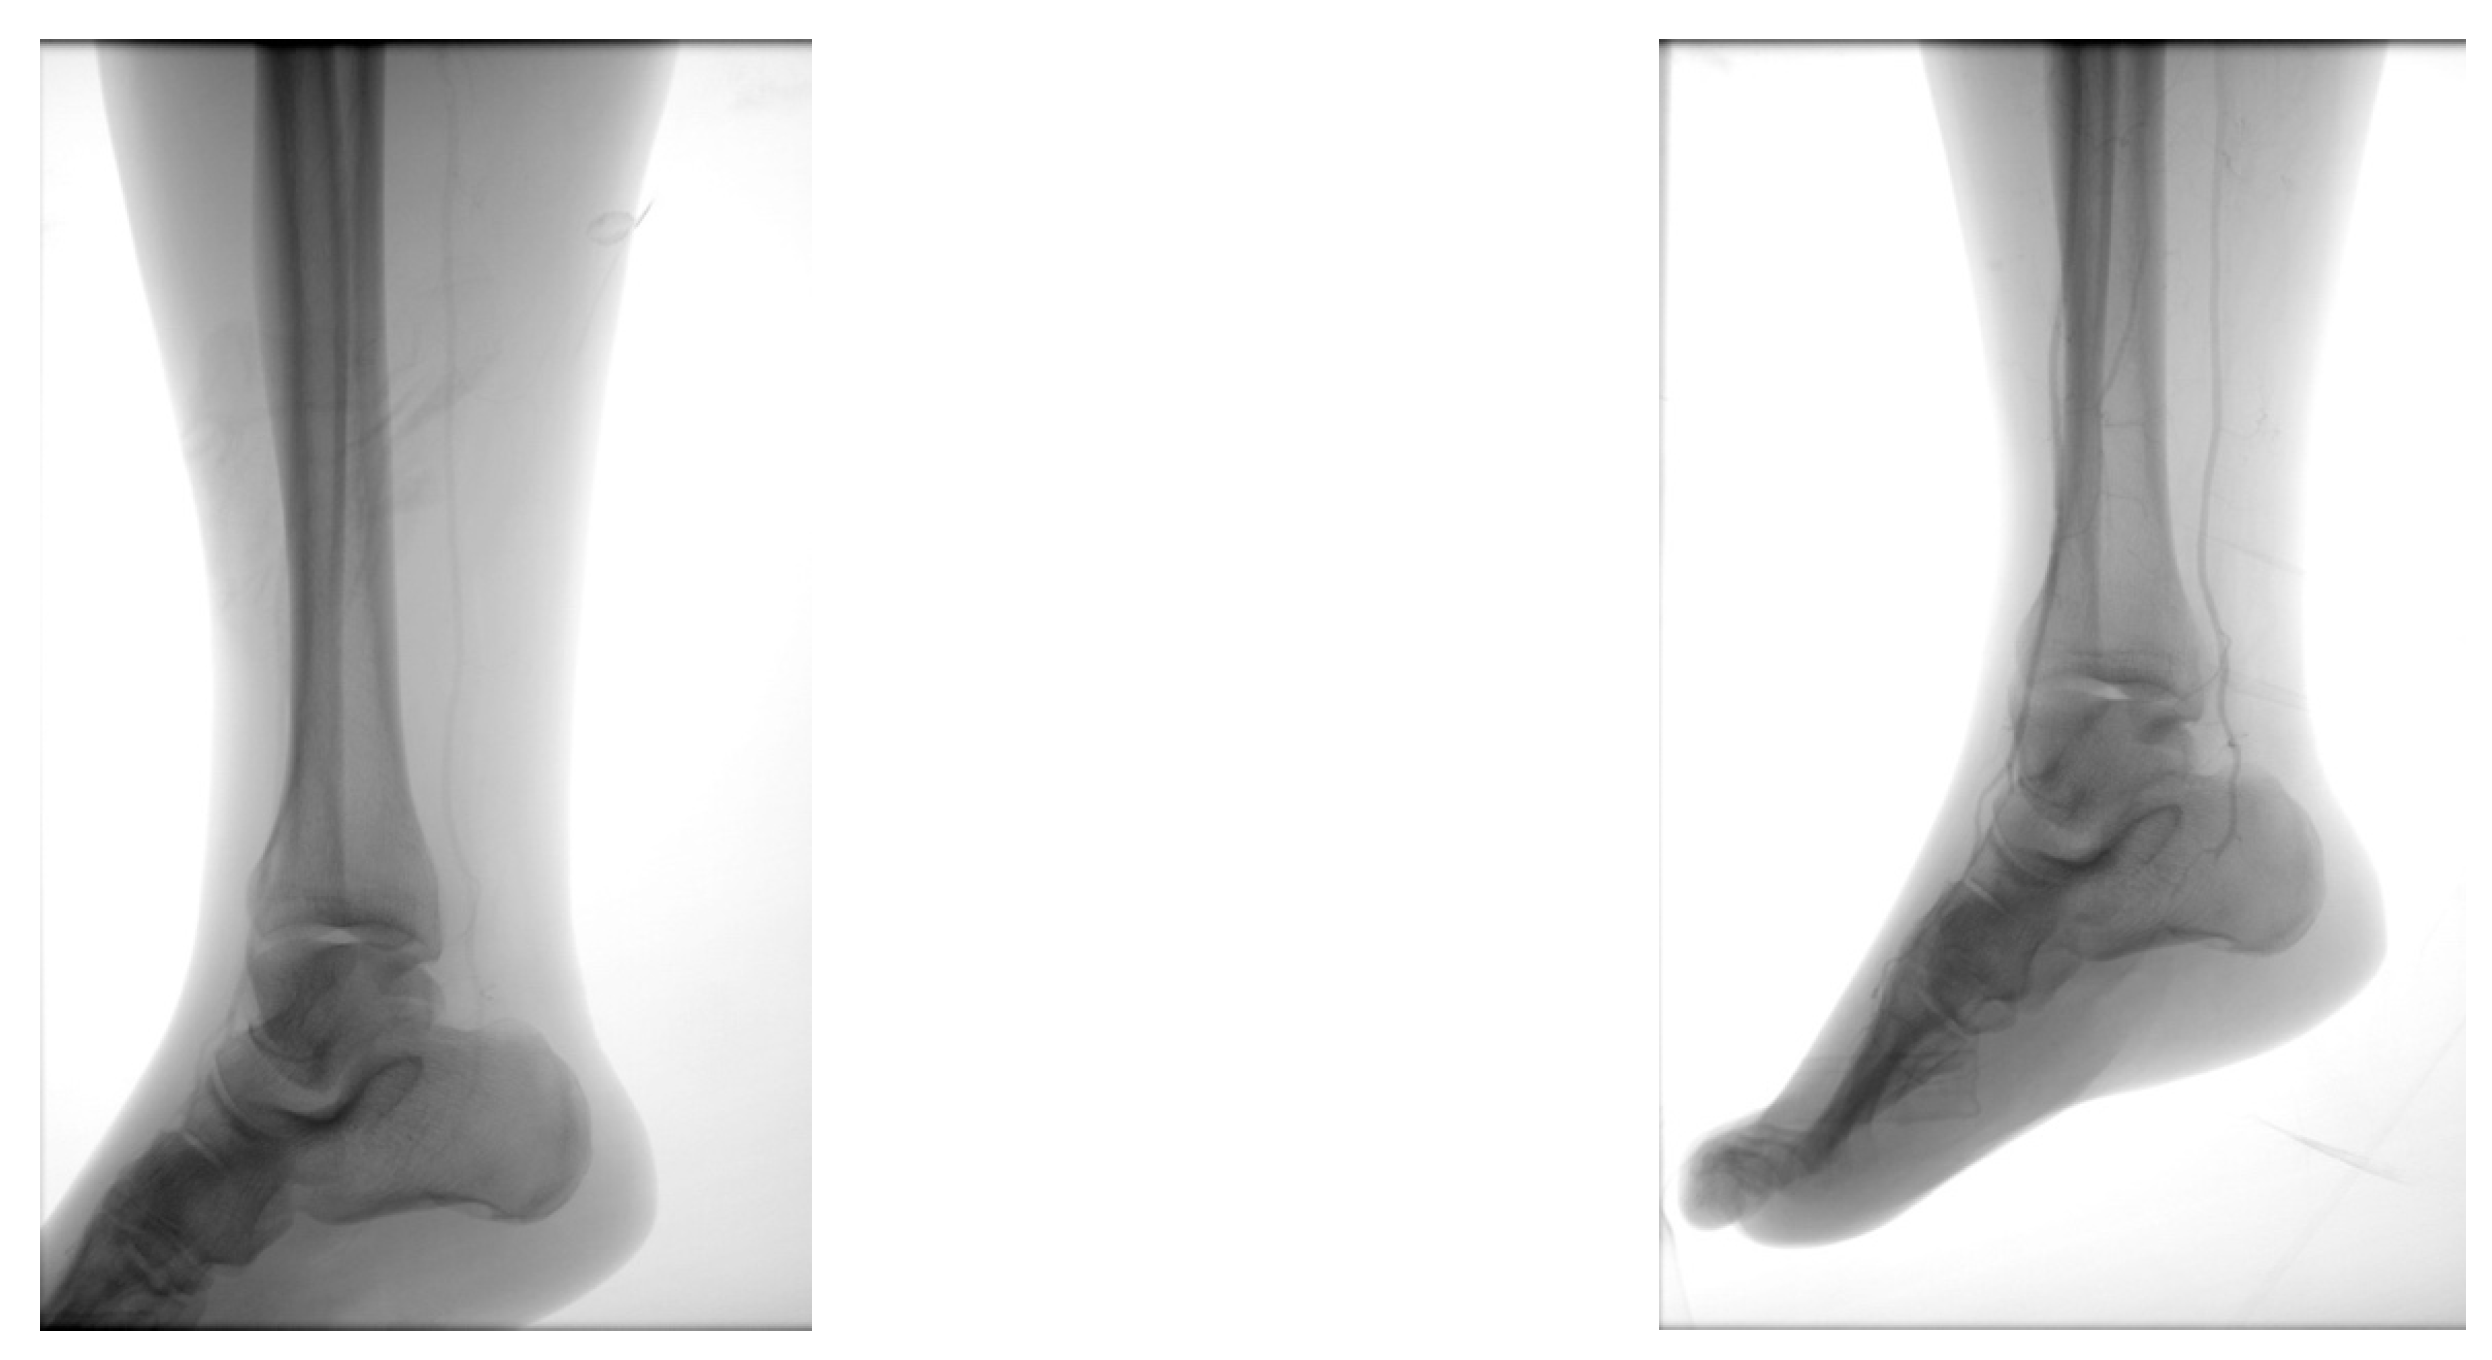

4.2. Case 2—Indirect Revascularization-Major Amputation